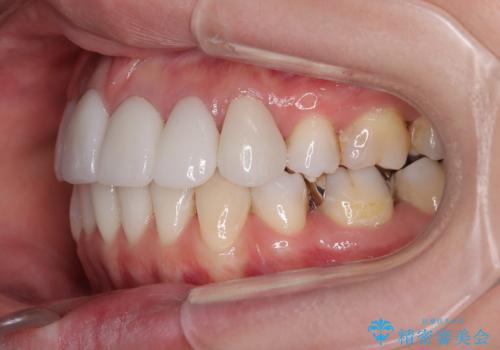

- 前歯の八重歯やデコボコを気にして来院された患者様です。

口元の突出感はありませんが、前歯の重なりが著しいため、目立ちにくい表側のワイヤー装置にて、上下左右の第一小臼歯4本を抜歯して矯正治療を行うこととしました。

上顎前歯4本は、以前むし歯により神経をすべて取り除かれており、その影響で既に変色を起こしている状態でした。

4本とも歯根部先端の骨が炎症により吸収していることがレントゲン写真から示唆されたため、矯正治療後に4本を再根管治療し、その後上顎6歯をオールセラミッククラウンにて補綴治療することとしました。

歯並びだけでなく、歯の色も明るくなり、すっきりとした口元の印象となりました。